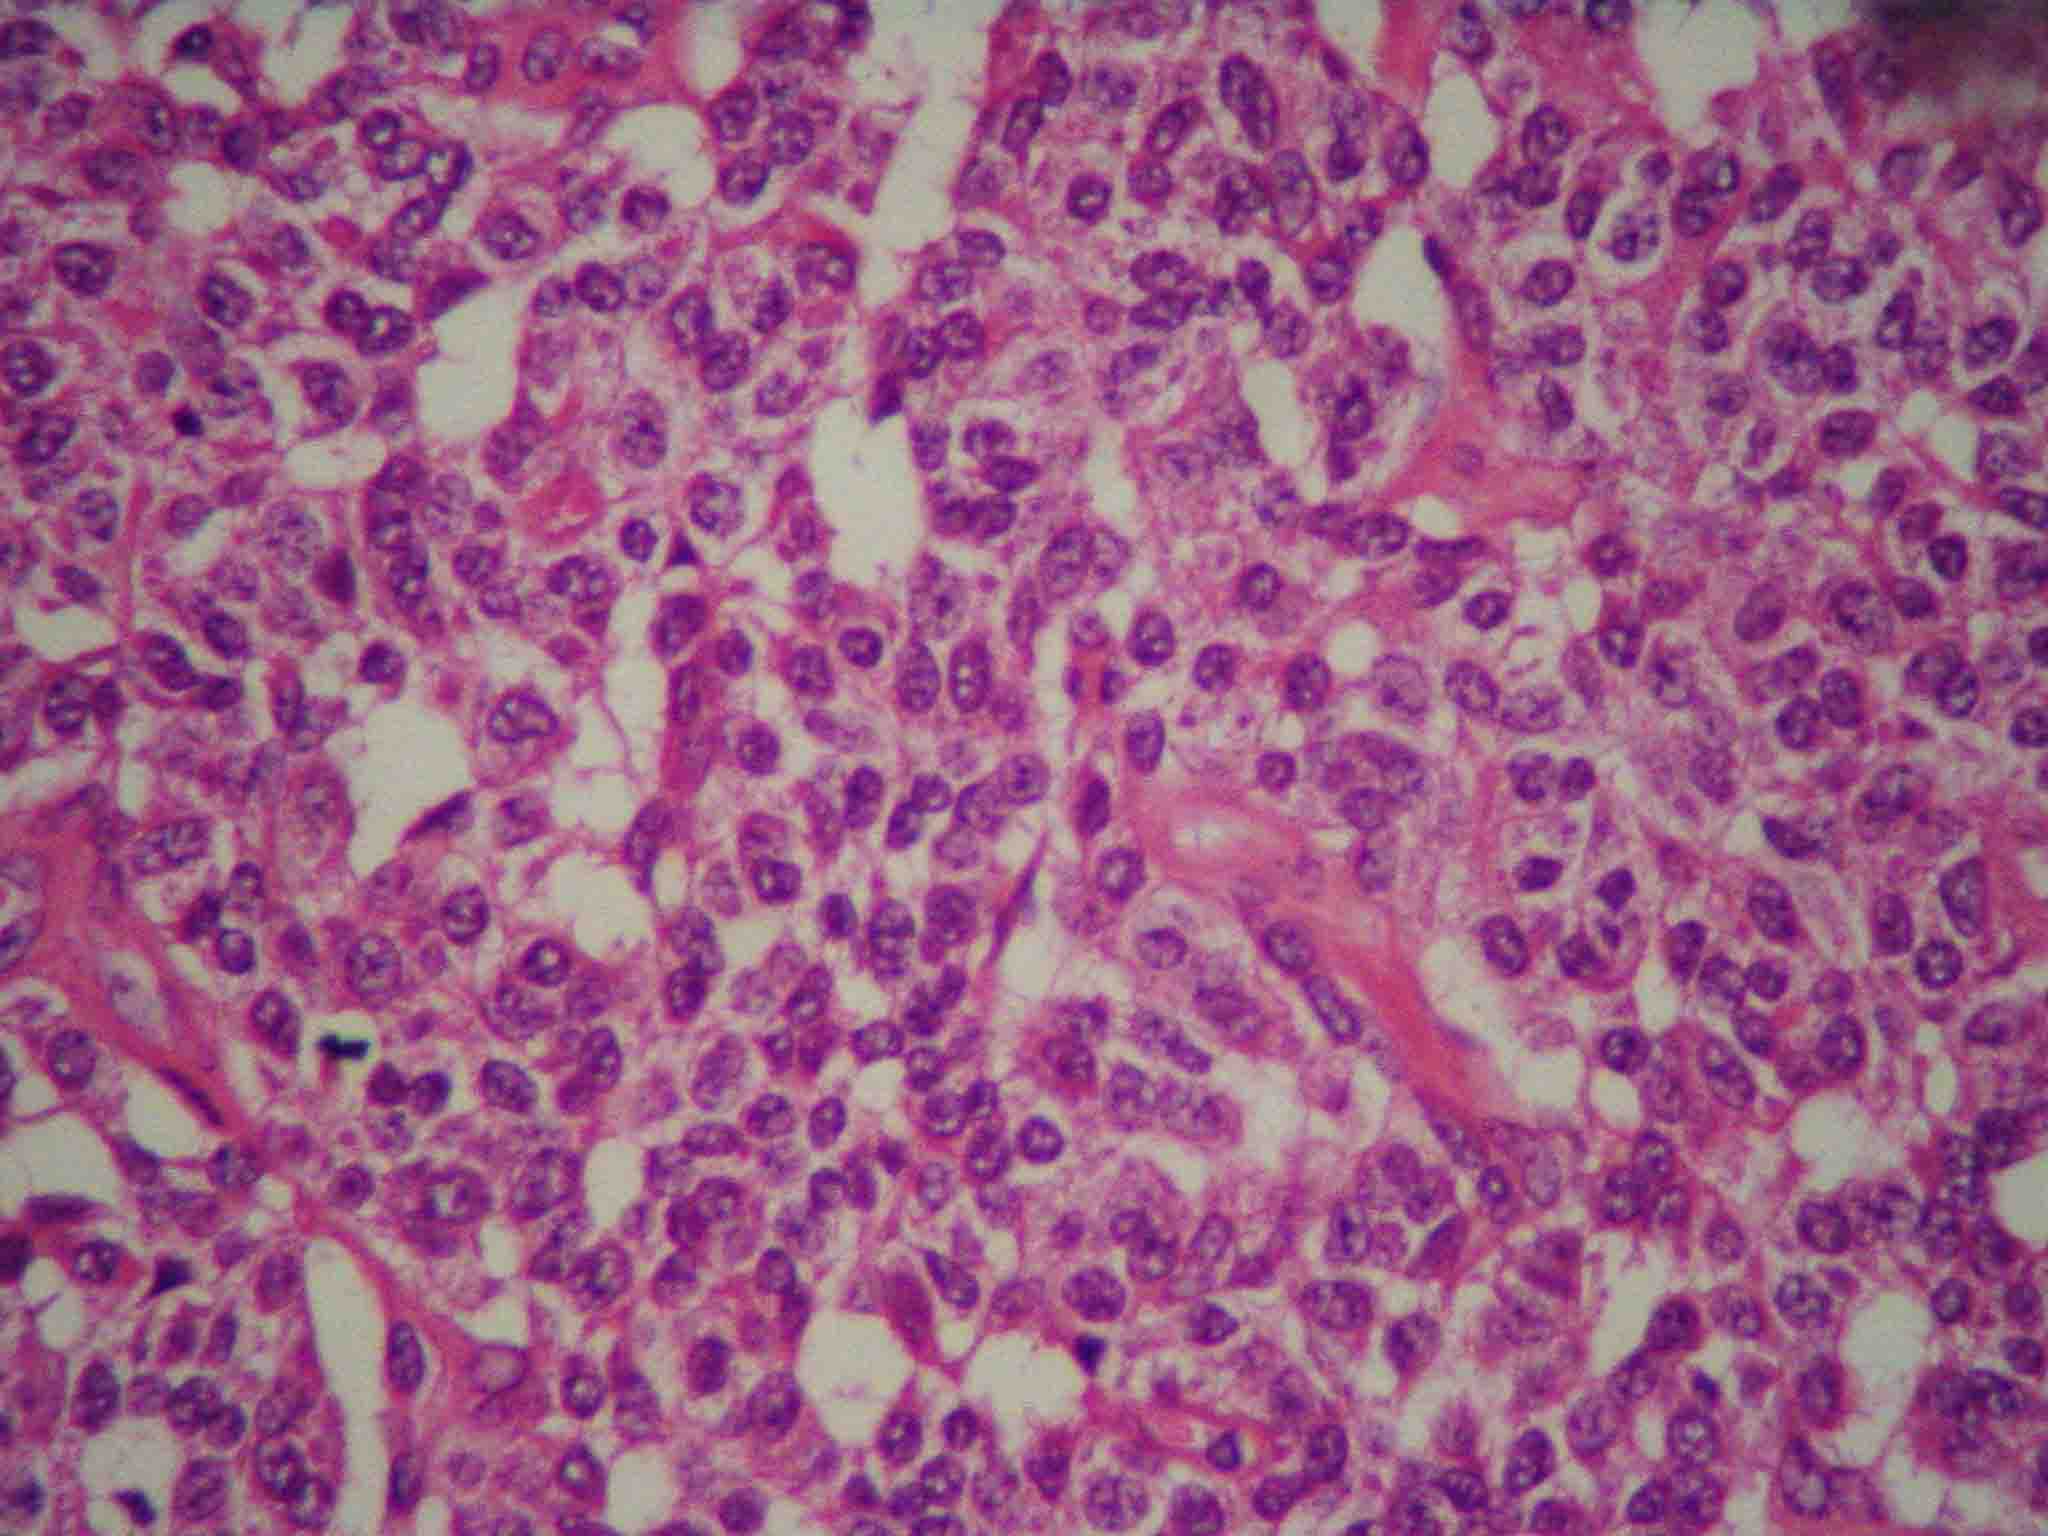

Carcinoid tumor is a serotonin-producing malignant tumor belonging to a class of neoplasms known as the neuroendocrine tumors. Carcinoid tumors of the lung are much less common and represent 1% to 2% of all lung cancers. The current classification of lung tumors recognizes bronchial typical carcinoid as low-grade neuroendocrine tumors. Symptoms are usually related to local compression and obstruction of the bronchial tree. Preoperative diagnosis is usually obtained without bronchoscopic biopsy. The authors report the case of a woman with typical carcinoid tumor in the left lower lobar bronchus, next to the secondary carina. It was treated with bronchoplastic resection, and associated to lymphadenectomy. The complete surgical resection remains the only therapy with curative intent in the majority of patients. Local relapse can be treated successfully with surgery, whereas distant metastases have a poor prognosis even after chemotherapy.Downloads

- HE.jpg (Português (Brasil))